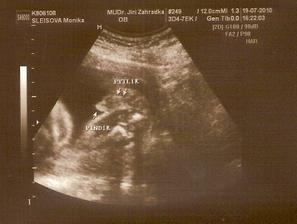

11.5. NT screening, jsem 13+5 a teď čekáme.....12.5. výsledky jsou v normě! 🙂